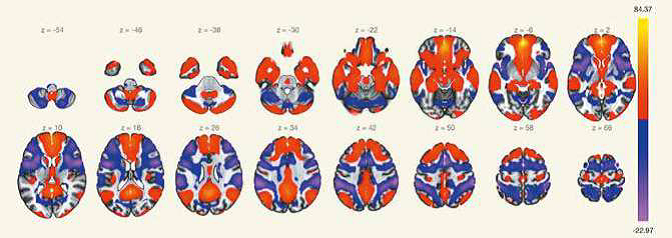

«Изменения коннектома головного мозга у пациентов с детским церебральным параличом в поздней резидуальной стадии при транслингвальной нейростимуляции». Обобщена МР-семиотика структурных и функциональных изменений головного мозга у детей со спастической диплегией. У детей с ДЦП в поздней резидуальной стадии преобладает снижение коннективности между компонентами сети выявления значимости и корой лобно-теменной области, компоненты которой также структурно связаны с компонентами сенсомоторной сети. При выполнении коннектометрического анализа трактов после ТЛНС (основная группа) выявлено повышение фракционной анизотропии более чем на 20 % (p < 0,001) в передней спайке (47 % от общего количества волокон), правом нижнем лобно-затылочном пучке (13 % волокон), левой поясной извилине (10 % волокон), правой зрительной лучистости (6,7 % волокон), мозолистом теле (6 % волокон), правой поясной извилине (1,3 %) (рисунок).

| Графическое представление результатов межгруппового статистического анализа: 2D-реконструкция проводящих путей белого вещества головного мозга с повышением ФА после ТЛНС в аксиальной (а), сагиттальной (б) и корональной (в) плоскостях. Показаны проводящие пути и часть их волокон, которые повысили ФА более чем на 20 % после комплексной реабилитации | ||

При выполнении коннектометрического анализа трактов после стандартной двигательной реабилитации (группа сравнении) статистически значимого повышения фракционной анизотропии (более чем на 20 %) не выявлено. При проведении диффузионной МРТ у детей с ДЦП в поздней резидуальной стадии выявлено статистически значимое снижение фракционной анизотропии в трактах белого вещества головного мозга, что свидетельствует о нарушении общих процессов миелинизации и, следовательно, скорости проведения нервных импульсов по их аксонам. Выявлены структурные и функциональные изменения головного мозга у пациентов с ДЦП после ТЛНС, которые свидетельствуют об усилении активации процессов нейропластичности.

Получены данные о наличии изменений с сети пассивного режима головного мозга при помощи использовании методики функциональной МРТ в покое. Наиболее выраженные изменения отмечаются в функциональной коннективности медиальной префронтальной коры (МПФК), которая играет важную роль в передаче соматосенсорной информации структурам, которые отвечают за моторные и висцеральные реакции, участвуют во внутренней системе вознаграждения и отвечают за принятие решений. Отмечается снижение функциональной коннективности между МПФК и правой дорсальной сетью внимания, правой супрамаргинальной извилиной, а также наблюдалось усиление функциональной связи с задней поясной извилиной, парацингулярной извилиной с обеих сторон, правой латеральной теменной корой, субкаллозальной корой, задней поясной корой, корой предклинья и правой супрамаргинальной извилиной. Отмечается латерализация изменений функциональной связности (преимущественно справа).

|

|

| а) | б) |

| Графическое представление результатов межгруппового статистического анализа, основанного на выборе зоны интереса (ROI-to-ROI): а – карты со схематическим представлением, совмещенные с анатомическим атласом головного мозга; б – 3D реконструкция карты положительных и отрицательных функциональных связей, совмещенных с анатомическим атласом головного мозга |

Пример карты SBC с медиальной префронтальной корой (МПФК) в качестве исходной зоны интереса, фМРТп (статистическая карта, T-тест)